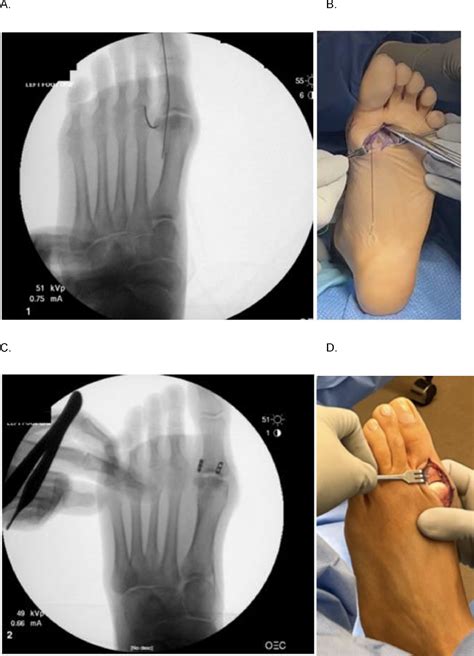

Surgical Intervention

If the MRI reveals significant joint instability, complete detachment of the plantar plate from the bone, or if the athlete is a high-level professional, surgical repair is often recommended. The surgeon will reattach the torn ligament to the bone using anchors. Following surgery, a prolonged recovery period involving a splint, boot, and extensive physical therapy is required before returning to sports.